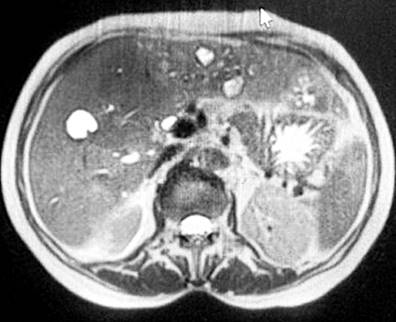

En su última visita, la paciente acude a la sala de emergencias con la sintomatología antes descrita, leucocitosis, aumento de las bilirrubinas, enzimas de colestasis (Tabla 1) e ictericia en la esclera y mucosas. Se valoró por el diagnóstico de colangitis, por lo que se realizó una colangiorresonancia, con la que se demostraron nuevos hallazgos a favor de múltiples lesiones quísticas intrahepáticas con captación anular del medio de contraste y dilatación de las vías biliares intrahepáticas, así como la extrahepática, hallazgos consistentes con enfermedad de Caroli. Se realizó una intervención con colangiopancreatografía retrógrada endoscópica (CPRE), en la que se efectuó una esfinterotomía previa canulación, y se observó la salida de coledocolitiasis y contenido seropurulento consistente con colangitis, y posteriormente se procedió a colocar una prótesis plástica de 10 Fr/9 cm (Figura 3).

Figura 3 CPRE en la que se observa contenido seropurulento consistente con colangitis. Fuente: expediente médico del paciente.